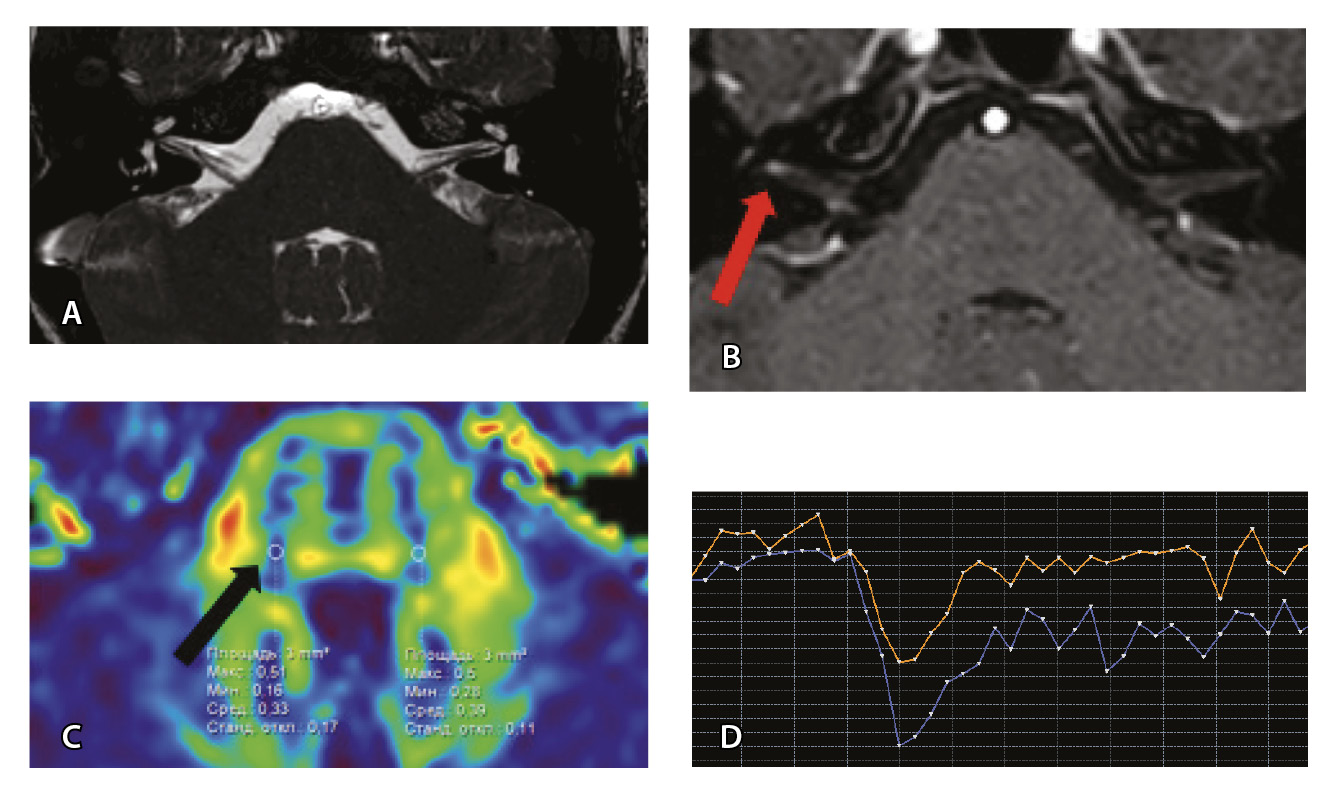

Рис. 3. Пациент Г. Магнитно-резонансная томография (МРТ) головного мозга: А – прицельная T2-SSFP на область мосто-мозжечкового угла; Б – Т1-взвешенное изображение с контрастным усилением; В – диффузионно-тензорная МРТ (фракционная анизотропия); Г – Т2*-перфузия (здесь и далее графики перфузии отражают зависимость повышения интенсивности МР-сигнала, то есть накопления контрастного вещества (вертикальная ось) от времени (горизонтальная ось), тем самым иллюстрируя основные показатели перфузии – relCBV, TTP, MTT). На изображениях T2-SSFP патологические изменения на уровне прохождения лицевых нервов во внутренних слуховых проходах (А), повышенное накопление вещества корешками лицевых нервов (Б) не определяются. Показатели фракционной анизотропии (В) и Т2*-перфузии (Г) на уровне моторных ядер лицевых нервов симметричны

Рис. 6. Пациентка З. Магнитно-резонансная томография (МРТ) головного мозга: А – прицельная T2-SSFP на область мосто-мозжечкового угла; Б – Т1-взвешенное изображение с контрастным усилением; В – диффузионно-тензорная МРТ (фракционная анизотропия, ФА); Г – Т2*-перфузия. На изображении T2-SSFP патологические изменения на уровне прохождения лицевых нервов во внутренних слуховых проходах не определяются (А). При контрастировании отмечается накопление контрастного вещества правым лицевым нервом во внутреннем слуховом проходе (Б, красная стрелка). На уровне моторных ядер лицевого нерва в заднем отделе варолиевого моста на изображениях ФА на стороне поражения отмечается минимальное уменьшение показателя ФА до 0,33 (В, черная стрелка) и признаки гипоперфузии справа (Г, оранжевый график) по сравнению с контралатеральной стороной (Г, синий график). Данный пример демонстрирует типичные изменения при мультипараметрической МРТ у пациента с параличом Белла

Рис. 7. Клиническое наблюдение 2, пациент 6 лет (А, Б, В, Г). Магнитно-резонансная томография (МРТ) головного мозга: А – прицельная T2-SSFP на область мосто-мозжечкового угла; Б – Т1-взвешенное изображение с контрастным усилением; В – диффузионно-тензорная МРТ (фракционная анизотропия, ФА); Г – Т2*-перфузия. На изображении T2-SSFP отмечается утолщение корешков лицевого, вестибуло-кохлеарного нервов во внутренних слуховых проходах (А, желтые стрелки) и интенсивное накопление ими контрастного вещества (Б, красные стрелки). На уровне моторных ядер лицевых нервов в заднем отделе варолиевого моста значения ФА симметричны (В), признаков гипо-/гиперперфузии не выявлено (Г).

Клиническое наблюдение 3, пациент 13 лет (Д, Е, Ж, З). МРТ головного мозга: Д – прицельная T2-SSFP на область мосто-мозжечкового угла; Е – Т1-взвешенное изображение с контрастным усилением; Ж – диффузионно-тензорная МРТ (ФА); З – Т2*-перфузия. На изображении T2-SSFP патологические изменения на уровне прохождения лицевых нервов во внутренних слуховых проходах не определяются (Д). В медиальном отделе правого полушария мозжечка определяется объемное образование, компримирующее стенку IV желудочка и задний отдел варолиевого моста без признаков васкуляризации (Е). На уровне моторных ядер лицевого нерва в заднем отделе варолиевого моста на изображениях ФА на стороне поражения отмечается минимальное уменьшение показателя ФА до 0,27 (Ж, черная стрелка) и признаки гипоперфузии (З, оранжевый график) по сравнению с контралатеральной стороной (З, синий график)